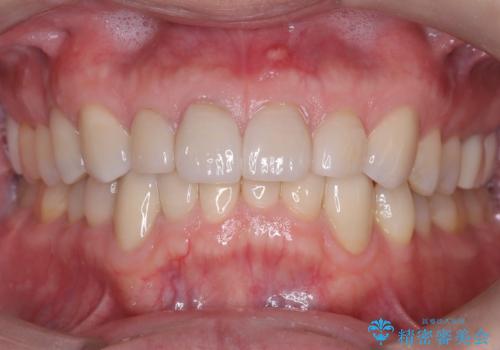

保険診療の黄ばんできた前歯をオールセラミッククラウンで自然な歯に